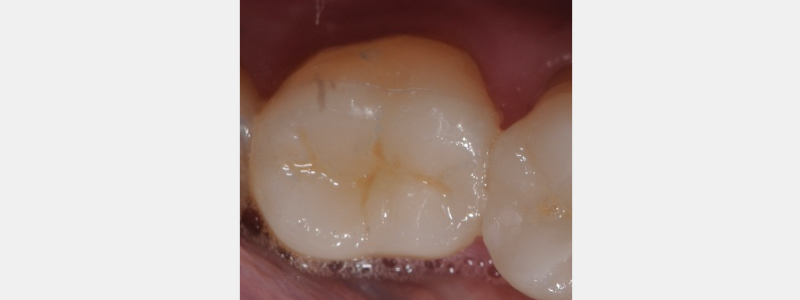

With the dentin primed, the bonding resin may be applied as “the cement.” Resin is applied with a micro brush to both the enamel dentin primed surface and the intaglio (inside aspect) of the provisional. With the provisional seated, the excess resin is wiped and the provisional is light-cured to place. Additionally, a flowable composite may be placed inside the provisional to help create a more intimate (filled) connection to the tooth. The patient is instructed to “pull” the floss through the contact rather than “snapping” the floss out from under the contact point.

At the time of ceramic restoration insertion, the provisional is removed by wedging a small excavator or scaler between the contact point of the adjacent tooth. Before processing the ceramic try-in, the enamel and dentin’s etched and bonded surfaces must be lightly abraded.

One can use a fine football-shaped diamond rotating at low speed to clear the surface of resin tags. Care must be taken not to contact the preparation enamel margins. Alternatively, the occlusal surface may be “micro-etched” with air particle abrasion. The fit and stability of the ceramic restoration can now be evaluated.